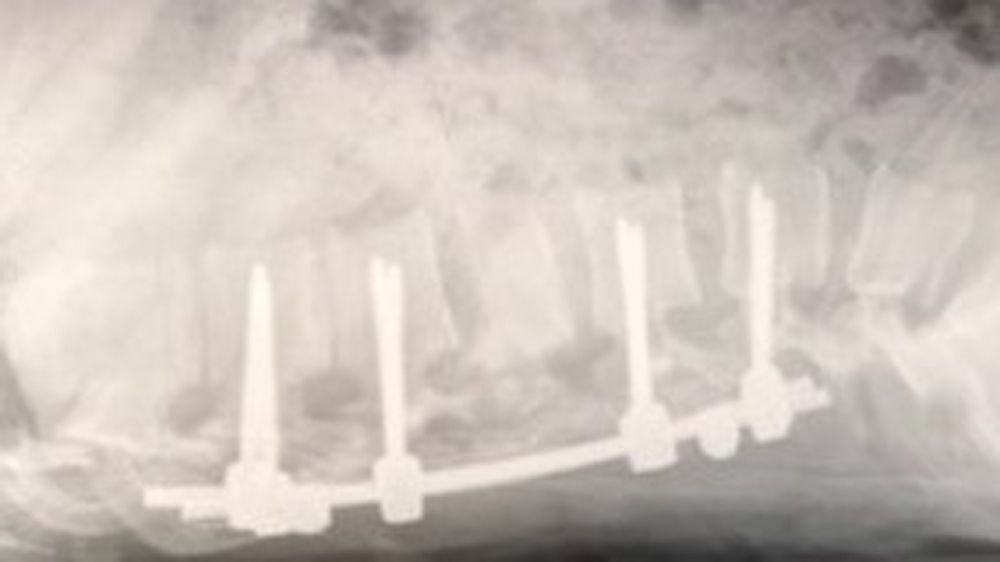

“Doctors told me I'd broken my back in four places, punctured one of my lungs, broken six ribs and ripped a major artery in my stomach, which resulted in me losing four pints of blood," he said.

“They told me they'd managed to set the spinal break with two large titanium rods, running down the middle of my back to my lower back.